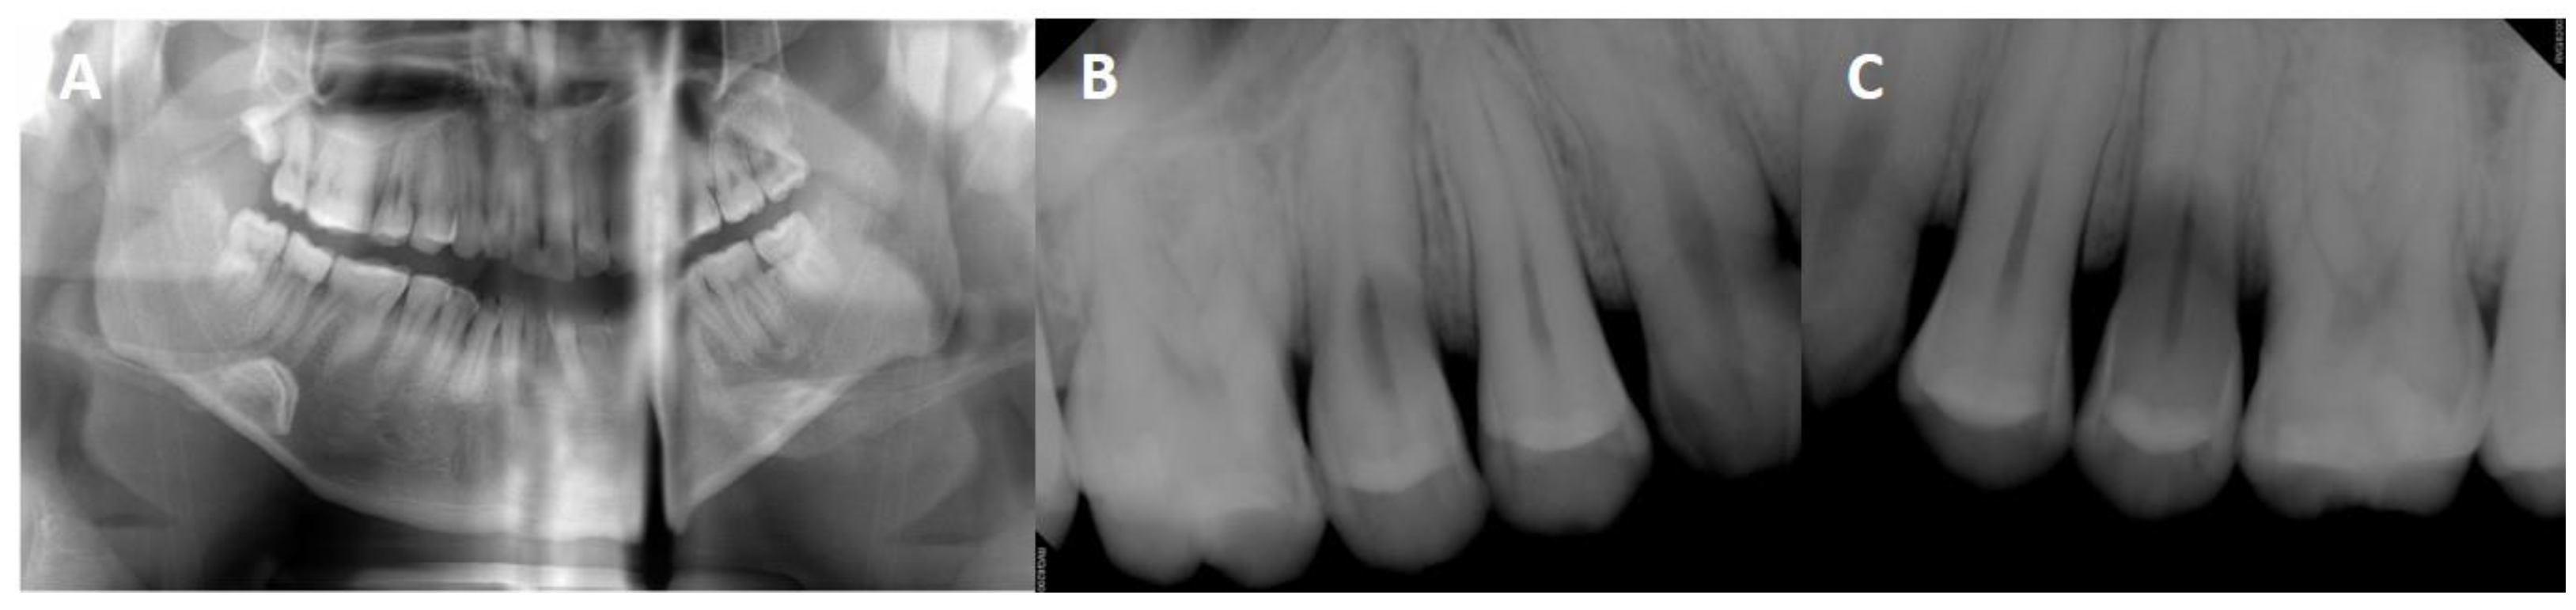

2. Case Report